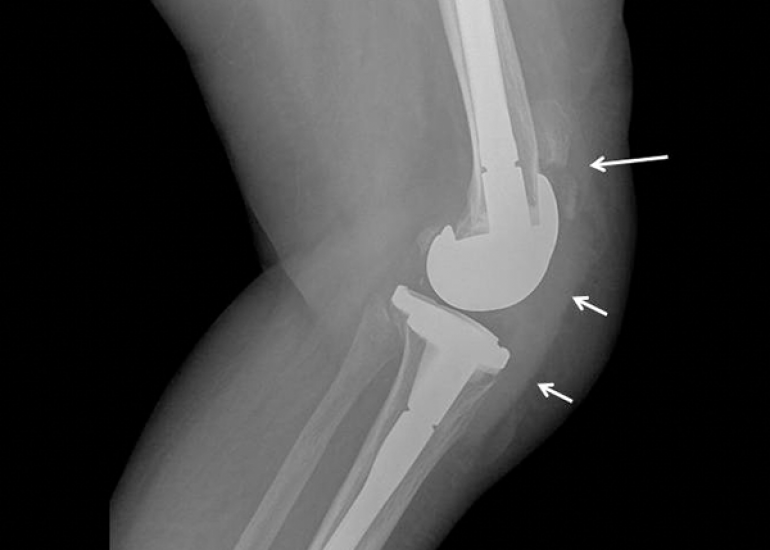

Director (Orthopaedics & Joint Replacement) & Head of Unit-1, Max Smart Super Speciality Hospital, Saket